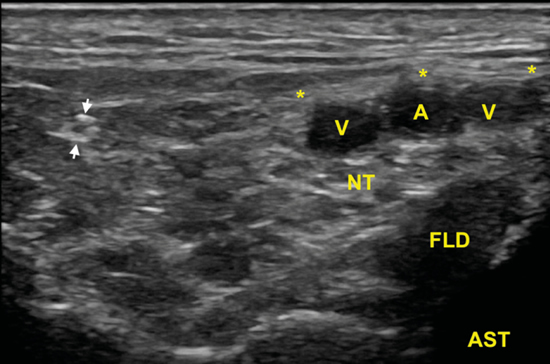

Figura 9. En esta imagen en eje corto, la rama calcánea (flechas) una vez que ha atravesado las láminas de la fascia crural (*) y se ha ido separando del nervio tibial (NT) que se encuentra debajo de los vasos (A, V), y sobre el tendón flexor largo del primer dedo (FLD) y el astrágalo (AST).